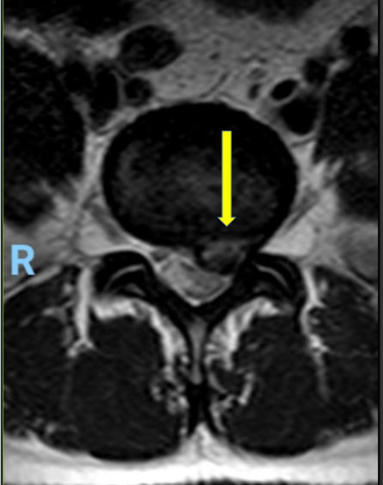

Hernia de disco lumbar extrusa L5 S1 (cortes

sagital y coronal en resonancia magnética)

Hernia de disco lumbar extrusa L5 S1 (cortes sagital y coronal en resonancia magnética)